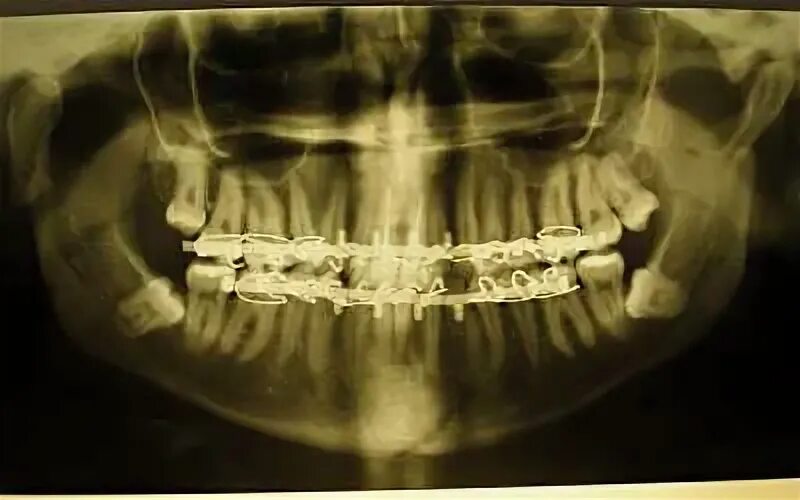

Переломы челюстей студфайл